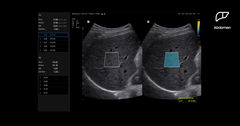

의사 숙련도따라 좌우되는 '간질환'…AI가 94% 찾아낸다[빠정예진]

송종호기자2025.11.22 06:01:00